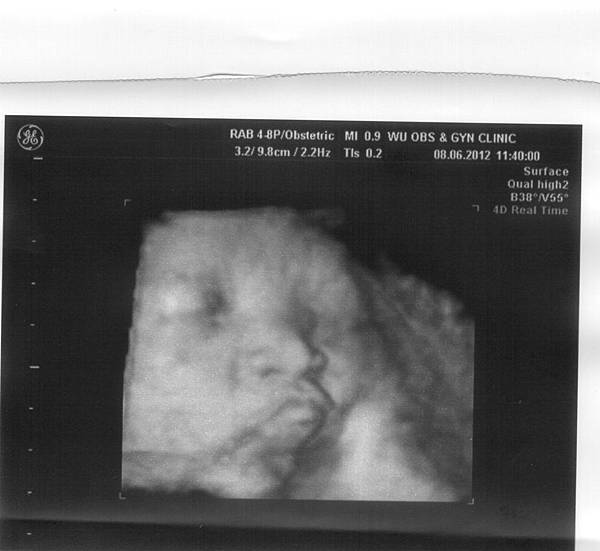

這次產檢也順便自費(900元)照了超音波,

老實說,感覺相當不好,

我們因為擔心照超音波要排太久,早早就抽號碼牌等候,

結果還是等了十幾分鐘才開始進行,

先是護理人員進行超音波檢測,但不知道是不是因為不熟悉機器,

所以還需要另個人在旁指導,偶爾才會跟我們說明「這是寶寶的頭、這是寶寶的耳朵」等等,

後來測出Bella已經2700了,著實嚇了我們兩夫妻,

看來Bella真的很認真在吸收養分耶!!

另外,Bella的頭還穩穩地擺在我右上腹,

我這才恍然大悟,這陣子覺得Bella會在我右上、左下腹部同時移動,

但感覺很像壞掉的秒針一直轉不過去,搞得我超痛的,

應該就是在嘗試把頭轉下來吧?!

不過可能遺傳到媽媽的懶惰病,

大概心想「嗯!我有努力過了,下不去就算囉~喔呵阿」,

所以乾脆就穩穩地坐在我肚子裡了吧XD

沒多久護理人員說,等等還會有醫生過來作檢查,

而我就繼續光著肚皮、躺在診療檯上等,

等等等,又等了十幾分鐘,終於有醫生進來了,

一樣的,非常不熟悉機器的操作,

不斷地邊在我肚皮上用力的滑來滑去,

邊問旁邊的人員操作方式,

看的我們兩一頭霧水,只能盯著螢幕發楞,

然後就結束了!!!!就這樣結束了耶!!!!???

醫生要離開前才丟一句,「啊!羊水量很正常。」

整個就是無言到了極致啊!!!

莫非是我們被吳婦產科寵壞了?

認定醫生都會溫柔地使用超音波,也邊耐心的解釋寶寶的狀態嗎?

唉唉,大醫院真的是讓人失望啊(攤手)